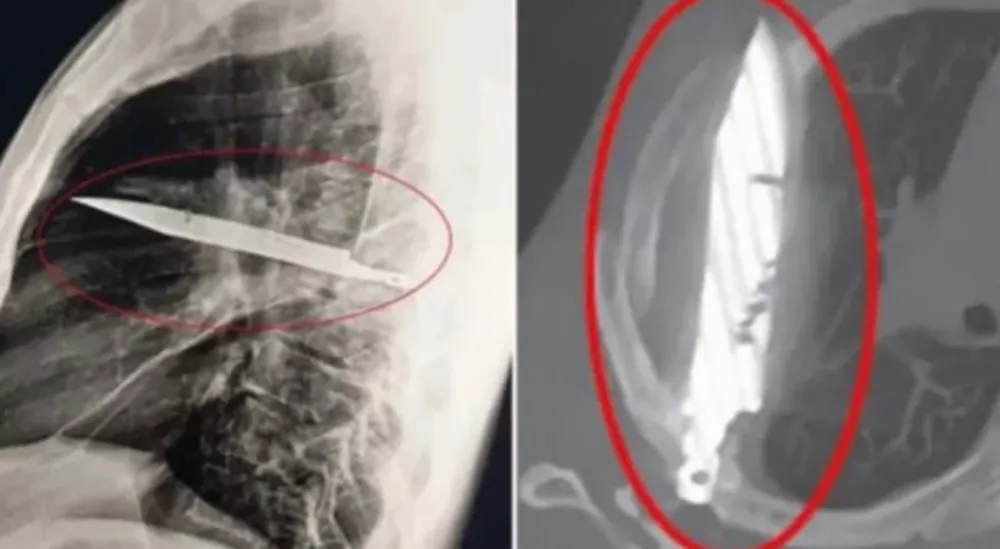

O homem relatou que havia se envolvido em uma briga. Na ocasião, sofreu ferimentos no rosto, costas, peito e abdômen – Foto: Reprodução

Porém, foi somente agora, anos depois, ao buscar ajuda por conta da secreção, que o verdadeiro impacto do episódio veio à tona. Um exame de raio-X revelou uma lâmina metálica alojada profundamente no tórax, atravessando a escápula direita, mas sem atingir órgãos vitais.